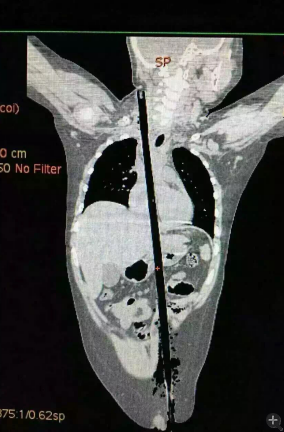

據相關知情人介紹,受傷男童24日晚在家中與小朋友一塊兒在墻頭上玩耍時,一不小心從高墻上跌落到了鄰家花圃中,讓人觸目驚心的是,該男童正好跌到了花圃中的一支長約63厘米,直徑約1.5厘米的竹棍上,竹棍自孩子的左側大腿根部直接插入腹腔并入胸腔直至右側頸部。

市兒童醫院組織專家團隊對孩子的病情進行檢查、評估后發現,竹棍由患兒左側大腿根部插入,經腹腔穿透胃、肝臟、膈肌入胸腔,并穿透患兒心臟,經胸腔入頸部,此刻不能拔除竹棍,因為去除竹棍會導致心臟、肝臟破裂大出血導致休克,危及性命。

由于竹棍自心臟的右心房膈面穿入心臟,并由右房近左房頂處穿出心臟,經右胸頂刺入右頸部,右心房破口處緊鄰右冠狀動脈,幸運的是胸腔內大血管無損傷,在體外循環輔助下,醫護團隊異物穿出處鋸斷異物,將插入心臟內的竹棍截斷拔除,修補心臟破損處,向上繼續尋找周圍組織的游離異物,見異物緊臨頸部大血管,經精細手術,終于抽出了異物。整個手術時間花了十多個小時。